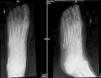

Examination of the skin revealed an ulcer with yellowish exudate, indurated margins, and atrophic skin in the adjacent areas. A blood workup revealed no leukocytosis or increased C-reactive protein levels. A substantial amount of tissue was taken from the margin and base of the ulcer for biopsy. Histopathology revealed collagenic fibrosis in the dermis and signs of vascular disease but no cellular atypia. These findings were compatible with radiation-induced dermatitis. Neoplastic processes were ruled out. Culture of the exudate revealed Vibrio alginolyticus (Fig. 1). Based on the results of the antibiogram, treatment was started with oral ciprofloxacin. However, the course was indolent, with the formation of a skin abscess (Fig. 1B) and development of osteomyelitis (Fig. 2) requiring admission to hospital. The lesion was debrided, even though no microorganisms grew in the culture. Antibiotic therapy was started with doxycycline and ceftriaxone for 10 days. Progress was good, and the ulcer resolved after 3 months.